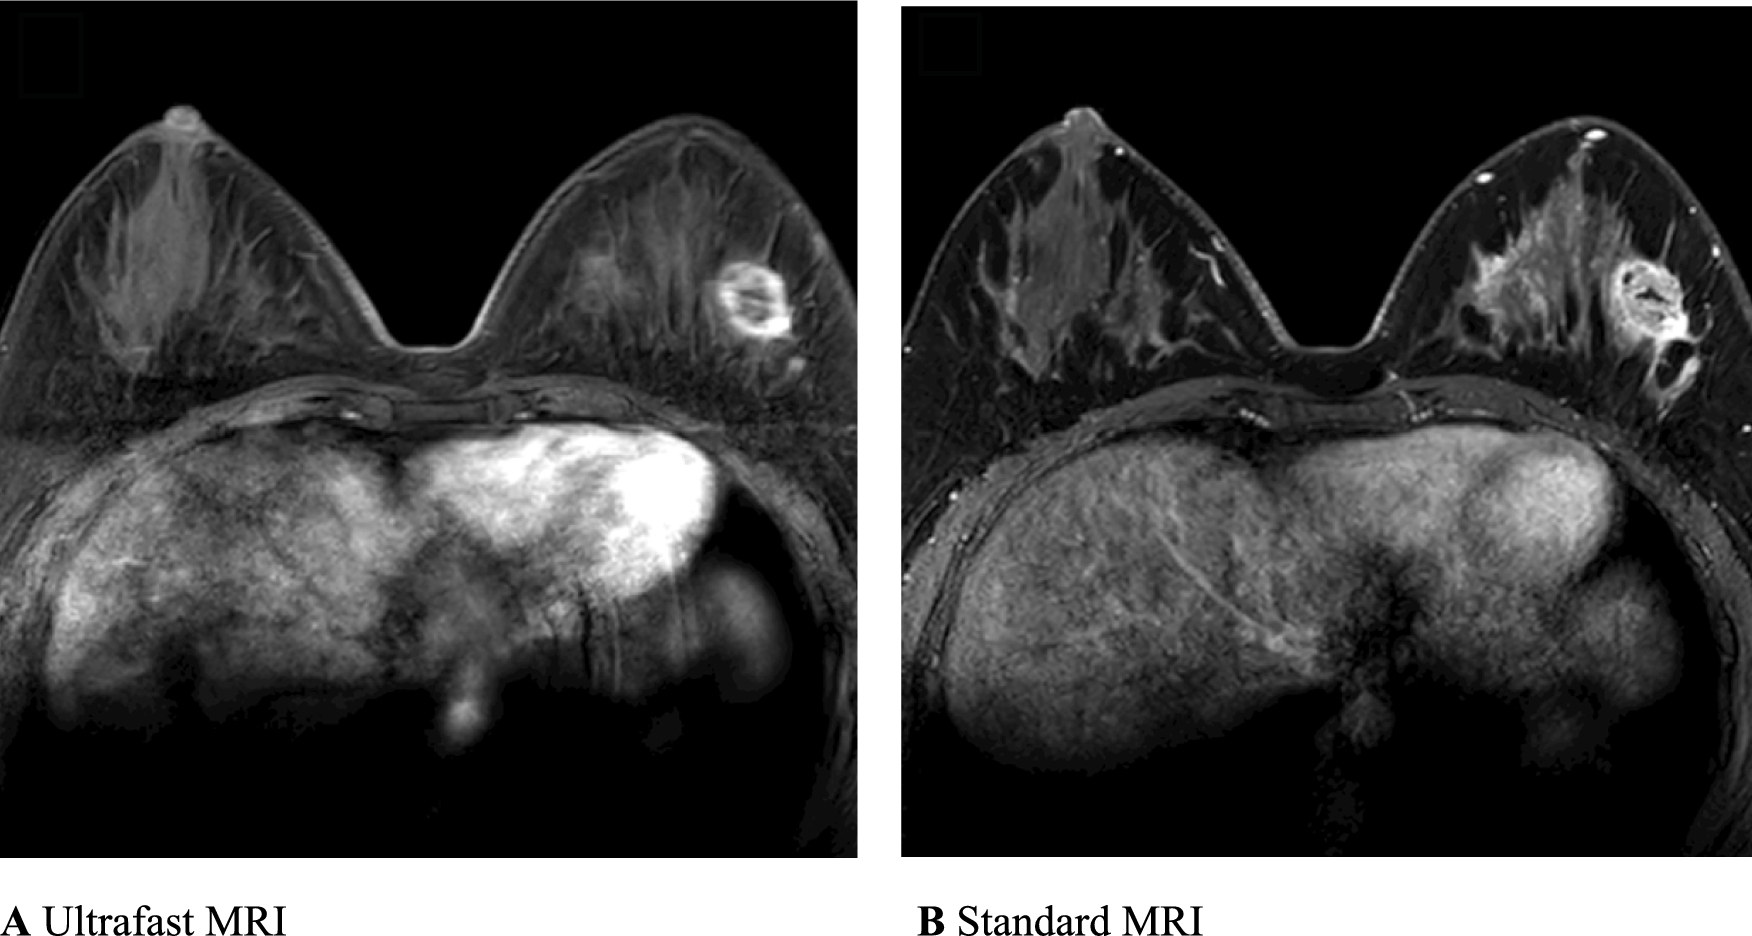

Our editorial team has also been impressed by the work of a Korean group that found that an ultrafast MRI radiomics model matched the performance of standard MRI in classifying hormone receptors, HER2 status, and molecular subtypes.